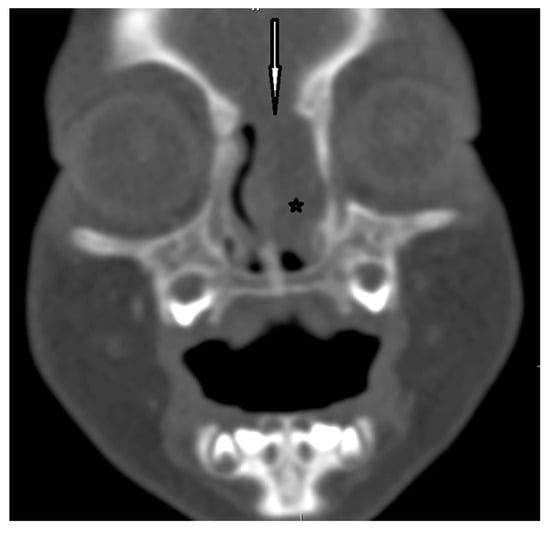

| Radiological characteristics | CT | No correlation between the particular location of the sinus ostium or cyst and the presence of intracranial extension; bifid crista galli and widening of foramen caecum (suggestive of intracranial extension); dermoid cyst—density of fat; epidermoid cyst—density of water | Bony defect may be revelaed | Developmental bony defect of the skull base |

| MRI | Variable signal intensity depending on the protein content; fat-suppressed T1-weighted images—differentiation between skull base defects and enhancing non-ossified cartilage of anterior cranial fossa; DWI—typically high-signal-intensity lesion with corresponding low signal intensity on ADC maps | Discontinuity with the brain parenchyma; variable visualization of a fibrous stalk connection to CNS; well-circumscribed, rounded, or polypoid mass—isointense or rarely hypointense to gray matter on T1-weighted imaging; neural tissue—more hyperintense on T2-weighted images to normal brain parenchyma in most cases; dysplastic tissue usually corresponds with no enhancement or moderate enhancement; noticeable enhancement at the lesion periphery | Herniation of intracranial tissue and its continuity with the brain | |